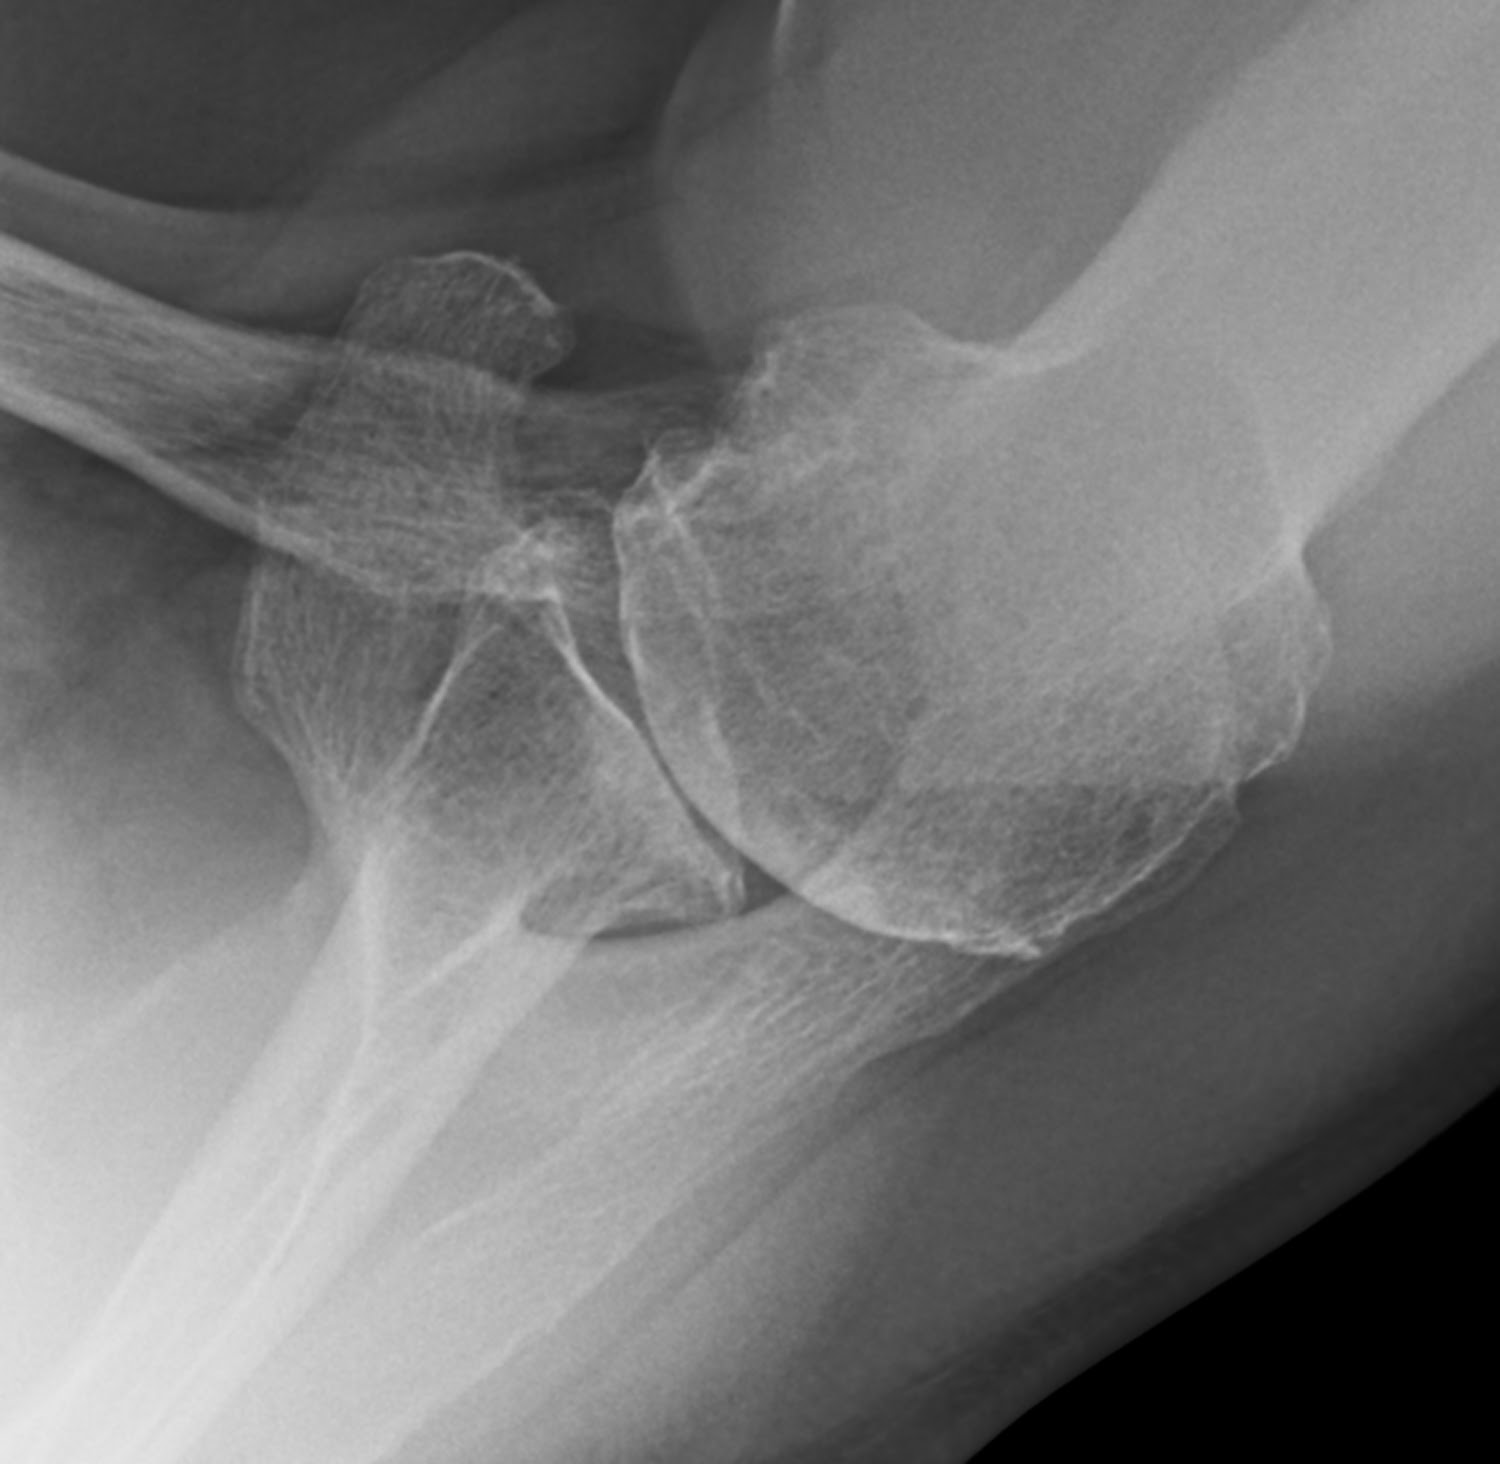

Rotator cuff tear arthropathy. (a) Conventional Xray, (b Shoulder X Ray Rotator Cuff Pain can happen because of: Tendinitis — inflammation of the rotator cuff tendons. rotator cuff tears are the most common cause of shoulder pain and result in loss of strength and loss of stability of the shoulder. rotator cuff tear arthropathy is a spectrum of degenerative disease that develops due to a rotator cuff deficient shoulder. the. Shoulder X Ray Rotator Cuff.